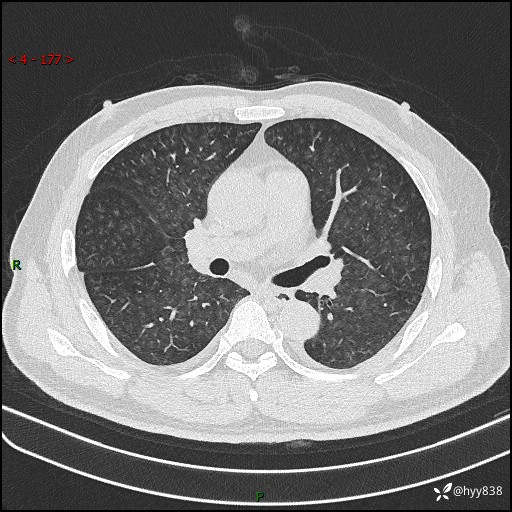

昨天肺结节门诊,“对门”呼吸科申请会诊病例,弥漫性肺部病变---结果公布~

简要病史:患者1周前无明显诱因出现咽喉部疼痛,随后出现咳嗽咳痰,起初干咳为主,后出现咳少许绿色痰,当时有发热,体温为39℃,无畏寒寒战,无胸闷胸痛,无活动后气短,无咯血,无鼻塞流涕,无全身酸痛,患者于诊所输液治疗后体温正常,但仍有咳嗽。患者3天前当地县人民医院就诊,患者仍有咳嗽,咳嗽较为频繁,咳嗽后出现头痛,伴有少许咳痰,随后出现活动后气短,1天前患者再次出现发热,体温最高为40℃,伴有畏寒寒战,伴有乏力、纳差,伴有胸闷不适,无咯血,无全身皮疹,无血尿、尿频尿急尿痛,无腹泻,诊断为“重症肺炎 感染性休克 肾功能异常 痛风”;予以抗感染(亚胺培南),抗病毒(奥司他韦)等对症治疗。患者复查胸部CT提示双肺病灶较前有所增多,建议上级医院就诊,门诊以“肺部感染”收入我科。 起病以来,患者食欲欠佳,大小便正常,睡眠、精神欠佳,体力下降、体重无明显变化。

辅助检查:CT

临床诊断:肺部感染

胸部HRCT